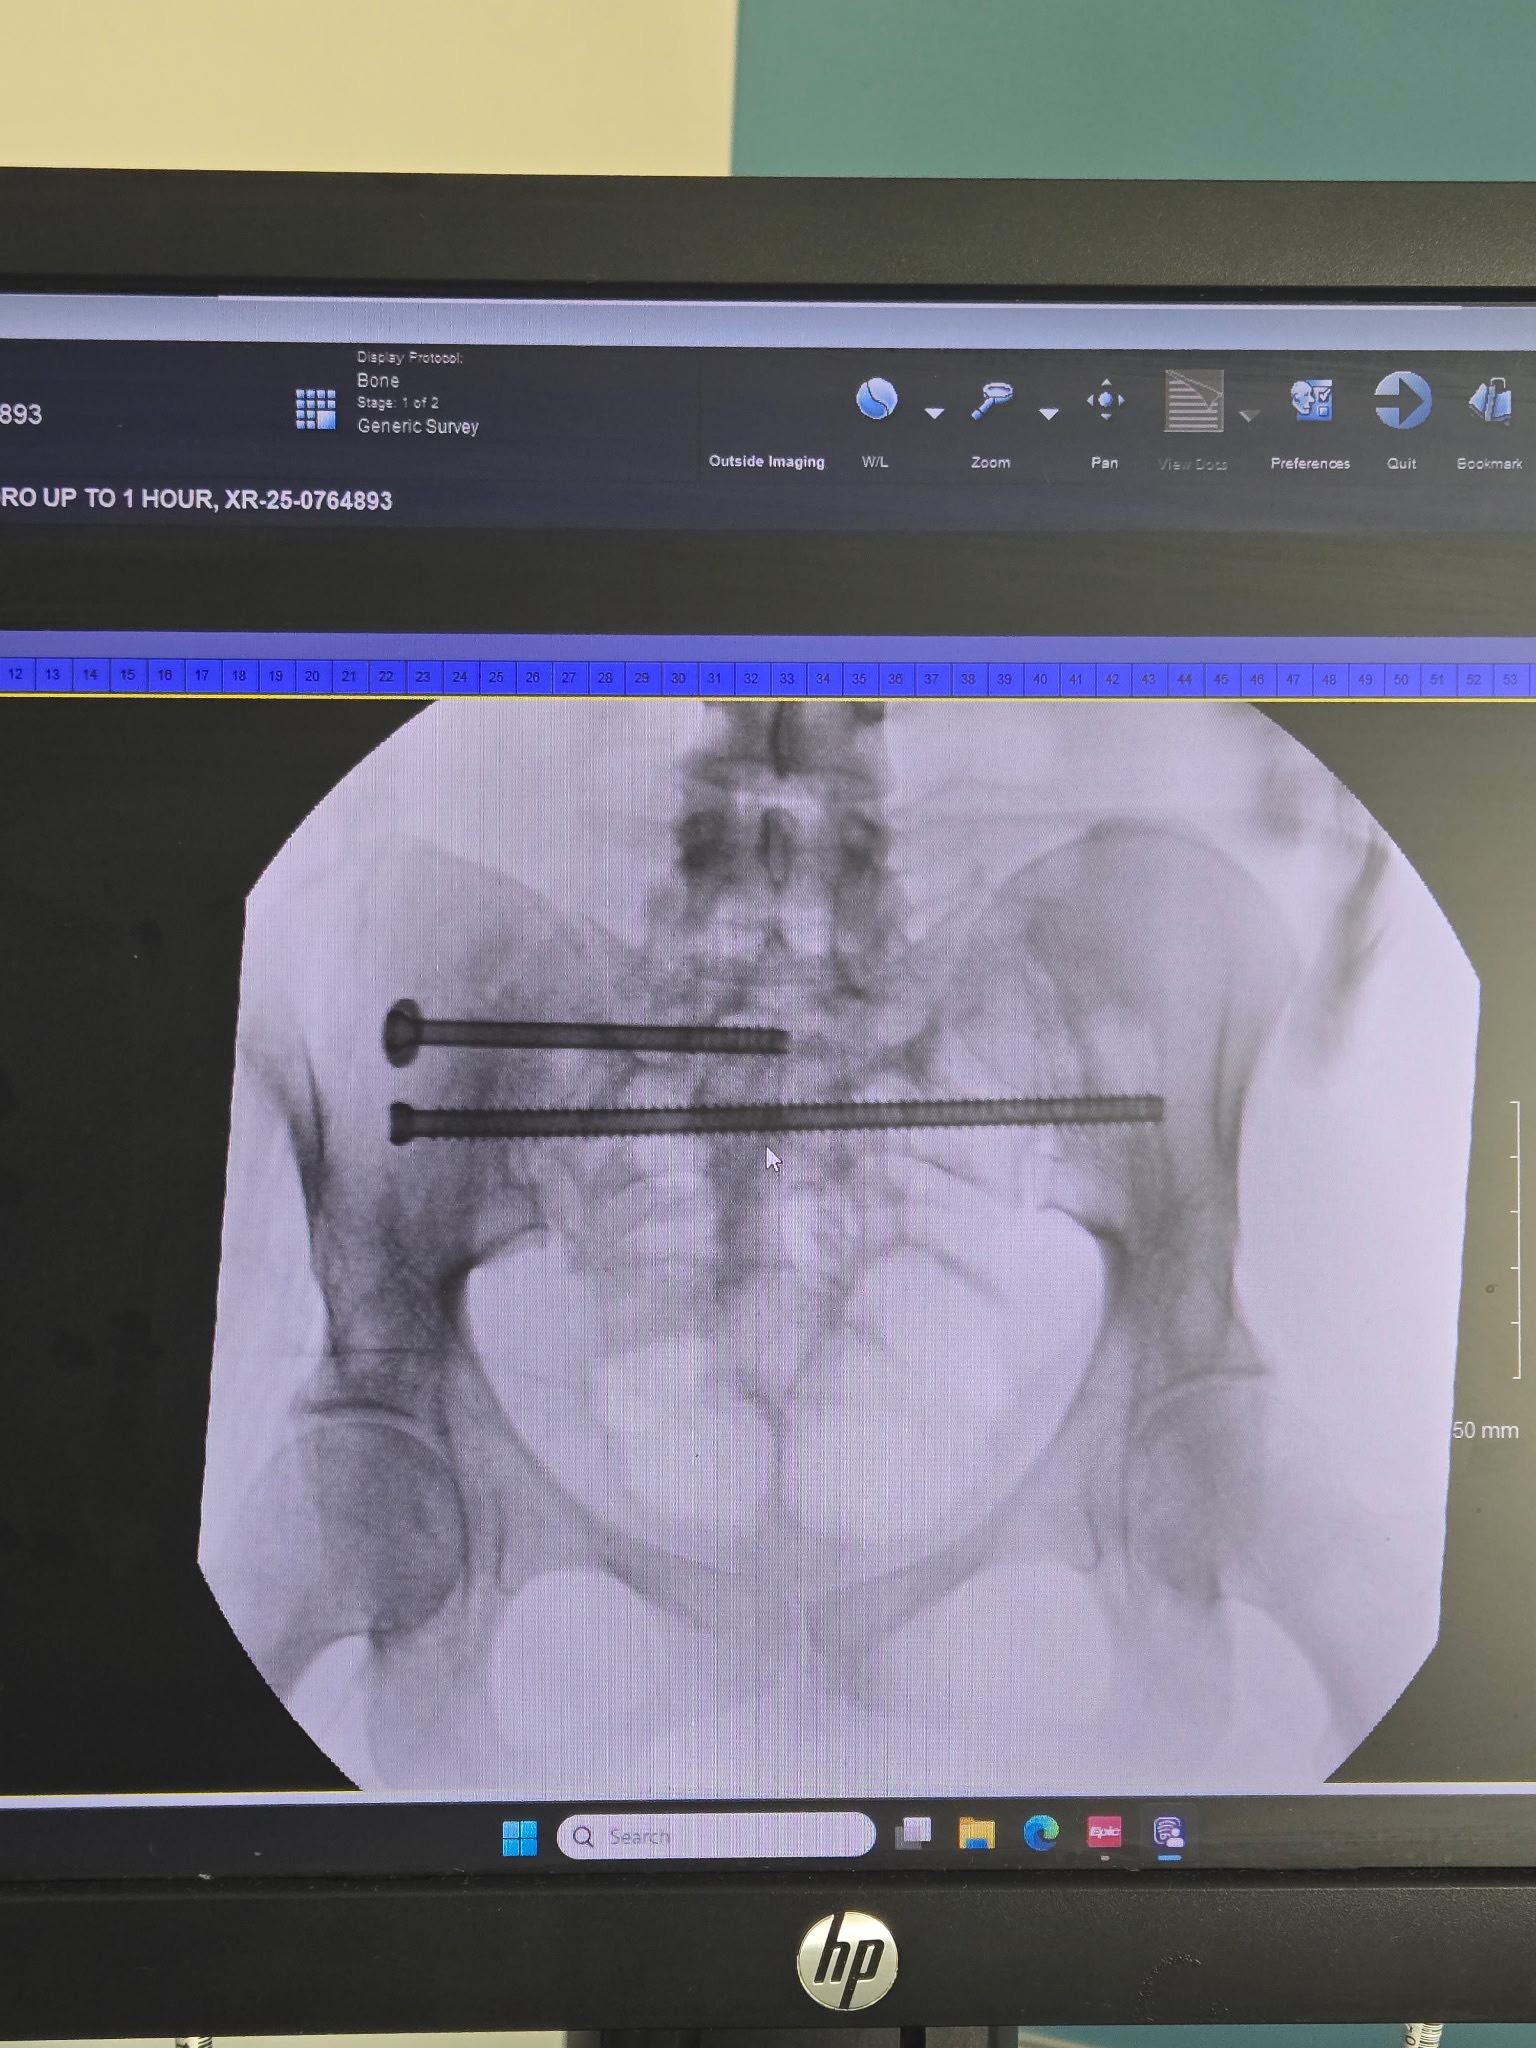

Thankful to the fire department that transported my sister to University of Cincinnati. On her way there she did seize but again thankful to the Emergency Department who was able to settle her seizure episodes down in. A CT Scan was done and she was diagnosed with a fractured and dislocated pelvis and will needed surgery immediately. Providers were concerned that with how small her pelvis is that the screws that were needing to be placed would cause nerve damage. But with the blessed hands of the surgical team, nurses, PCA, and whoever else was involved in Jayde’s care, she was able to come out of surgery successfully on Saturday morning the 27th.